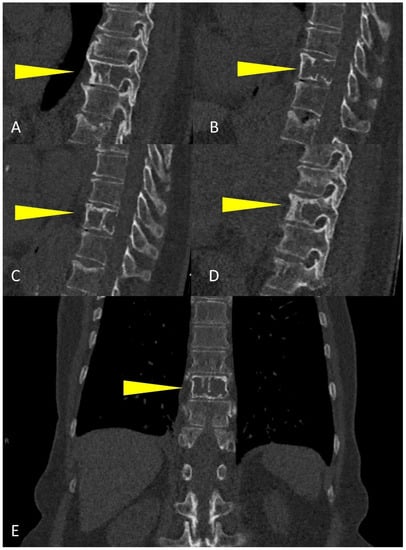

Whole-Body Low-Dose Multidetector-Row CT in Multiple Myeloma: Guidance in Performing, Observing, and Interpreting the Imaging Findings

3. WBLD-CT Imaging Findings and Evaluation